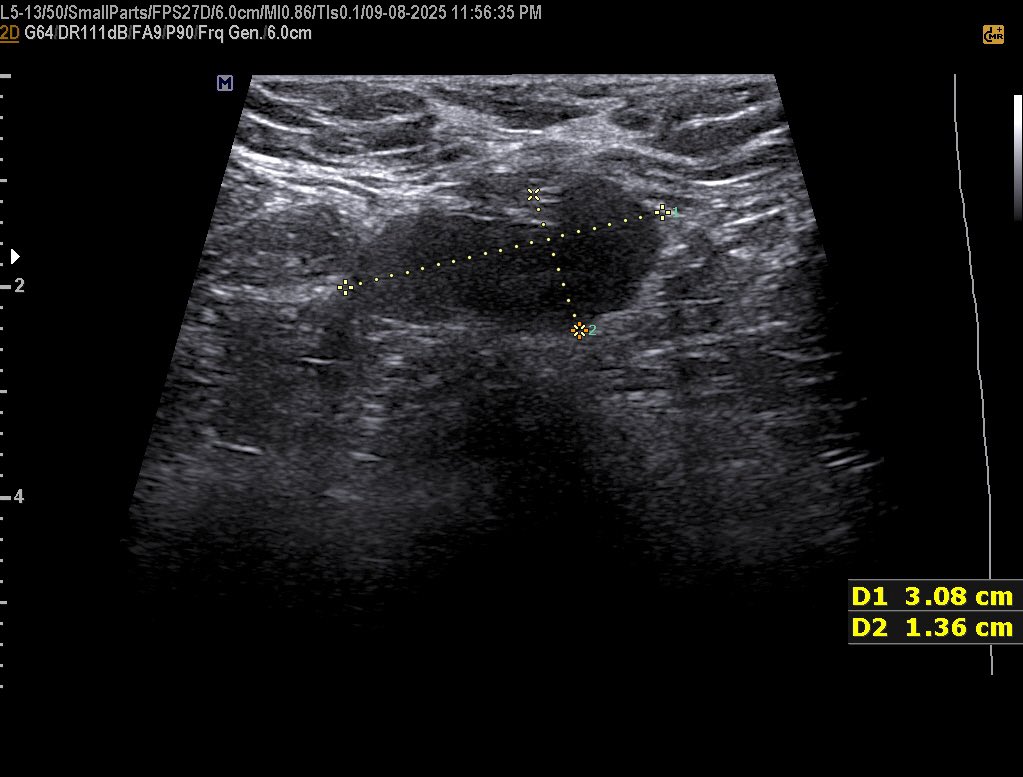

42 years female presented with a palpable painless hard and fixed Breast mass since 1 year BI-rads? #EchoTech @ABCDEcografia @dmiguelmolina @Omkolsoumyahoo1

42 years female presented with a palpable painless hard and fixed Breast mass since 1 year BI-rads? #EchoTech @ABCDEcografia @dmiguelmolina @Omkolsoumyahoo1